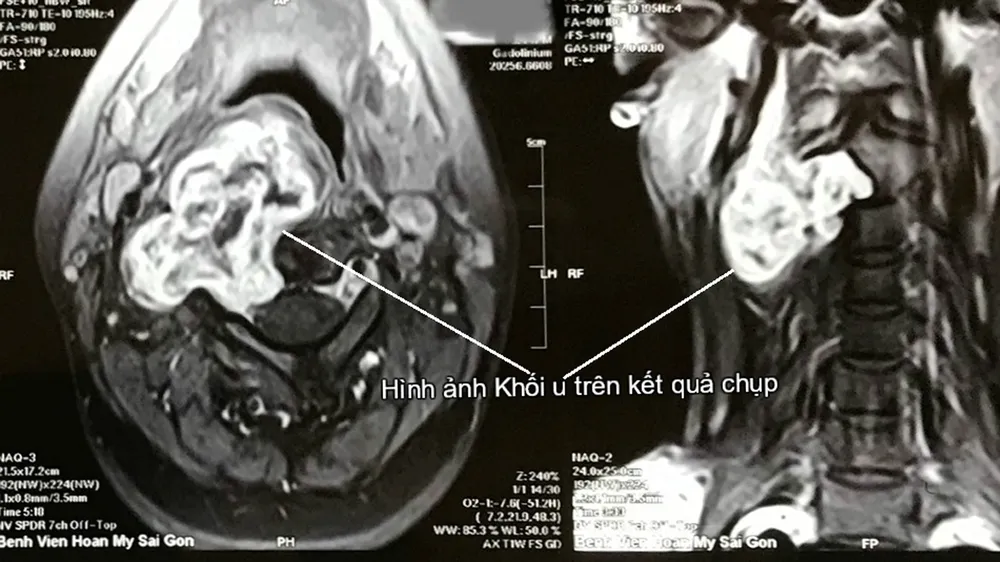

Bệnh nhân nhập viện trong tình trạng khàn tiếng, giọng nói bị đứt hơi với khối u vùng cổ bên phải. Kết quả chụp MRI cho thấy bệnh nhân bị u bao dây thần kinh C2 - C3 bên phải, xâm lấn thành họng bên phải, đường kính 6cm.

Giúp bệnh nhân bỏ u bao dây thần kinh cột sống cổ xâm lấn  ảnh 1